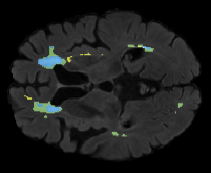

We evaluated our method in segmenting WMH from T1-w images using: a) Synthesized FLAIR images by treating the synthesis as a preprocessing step – we will refer to this method as offline synthesis; b) Synthesized FLAIR images using the proposed method, and c) without any synthesis – we will refer to this method as Unimodal. Baseline methods are illustrated in Figure 2

Table 2: Segmentation results for all proposed methods, each column represent a different slide in the image, blue areas are regions which were correctly labeled, false positives are shown in green, and false negatives in yellow

In order to better understand the above results, we visually analyzed the output segmentation performed for each method. Table 2 shows the results for three different slices (one slice per column). As illustrated, the proposed method is able to produce less false positives. It is also important to note that, unimodal segmentation is the one that produces more false positives, showing the advantage of using synthetic data. Regarding the nature of false positives, it can be easy to see in the third column a large number of false positives are on the border of periventricular lesions for the Unimodal method in comparison to the proposed method. Also from the first and second column, it can be observed that Unimodal tend to produce more small regions of false positives near to cortical areas. Removing such false positives requires additional post-processing steps, therefore, it is of value avoid this kind of over-segmentation. It can also be noted that synthesis methods tend to produce the same kind of false negatives, this may be due to the blurring effects in synthesized images since the information available during testing is limited – which otherwise is available from a FLAIR sequence.